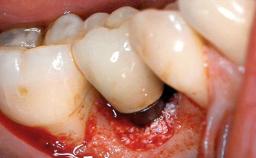

A 73-year-old woman was referred to the Division of Periodontology (University of Geneva School of Dental Medicine) after repeated unsuccessful treatment of a peri-implant infection. She was systemically healthy and did not smoke. The patient’s history revealed that, three years earlier, an immediate implant (Straumann Tapered Effect RN 4.8/4.1; Institut Straumann AG, Basel, Switzerland) had been inserted to replace the upper right central incisor. A metal-ceramic crown had been delivered using an adhesive resin cement. One year later, the patient had consulted another dentist due to discomfort in the soft tissues in the implant region. There was a suppurating peri-implant pocket, 10 mm deep. Peri-implant bone loss and excess luting cement were seen on the radiograph. The situation was treated with non-surgical debridement, amoxicillin, and repeated submucosal irrigation with a chlorhexidine digluconate solution. The patient was referred after the suppuration had persisted for several months.